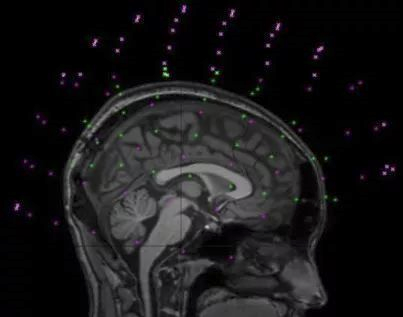

1.Feature detection: 特征检测

图像配准过程的一项重要任务。根据问题的复杂性,通常分为手动或自动检测,但通常优先选择自动特征检测。

封闭边界,边缘,轮廓,线交点,角点,以及它们的代表点如重心或线末端(统称为控制点)可以作为特征。由特殊对象组成的这些特征必须易于检测,即特征将是物理上可解释和可识别的。

参考图像必须与浮动图像共享足够多的共同特征集合,而不受到任何未知遮挡或意外改变的影响。用于检测的算法应该足够稳健,以便能够在场景的所有投影中检测相同的特征而不受任何特定图像变形或退化的影响。

2.Feature matching: 特征匹配

该步骤基本建立在对待配准图像与在参考图像中检测到的特征之间的对应关系上。

除了特征之间的空间关系之外,还采用不同的特征描述符( feature descriptor)和相似性度量来确定配准的准确性。

必须合理地配置特征描述符,使得它们在任何退化时仍保持不变,与此同时,它们需要不受噪声影响且能适当区分不同的特征。